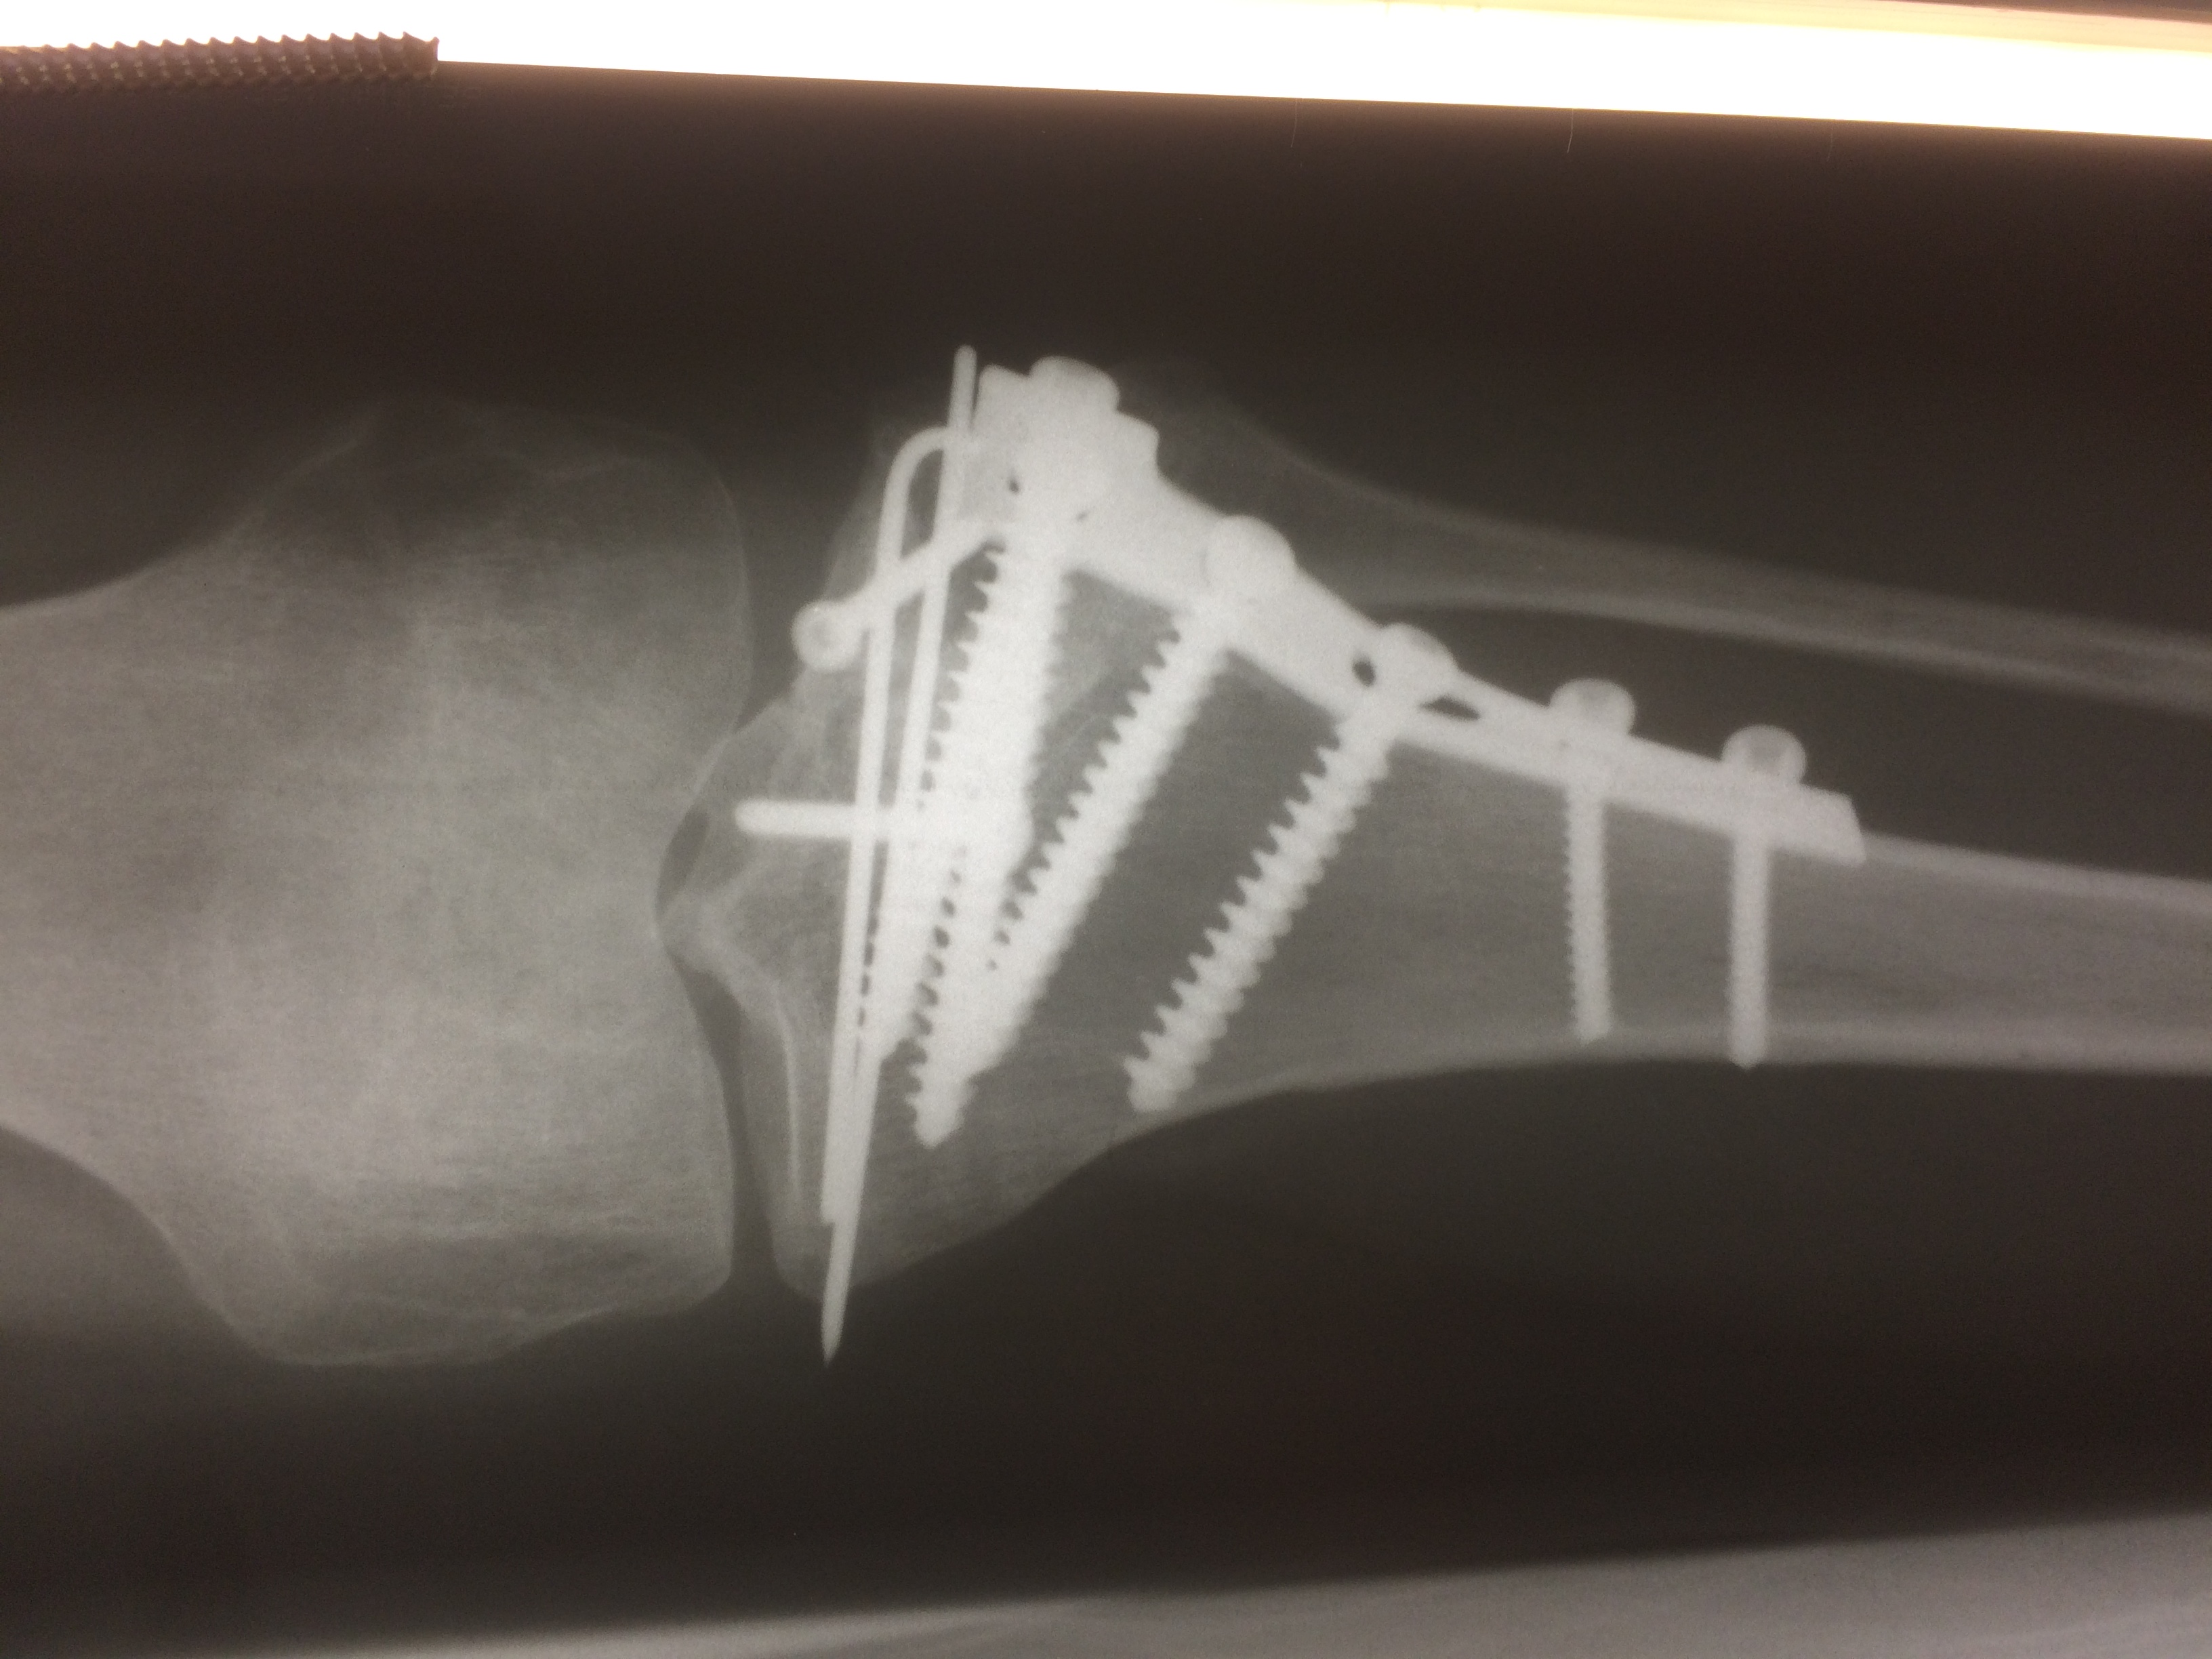

Использование материала Остеоматрикс при импрессионном оскольчатом переломе наружного мыщелка большеберцовой кости по типу Schatzker II

Использование материала Остеоматрикс при импрессионном оскольчатом переломе наружного мыщелка большеберцовой кости по типу Schatzker II.

Операция - открытая репозиция, остеосинтез большеберцовой кости опорной пластиной с костной ксенопластикой маетриалом "Остеоматрикс". На контрольных снимках в три и шесть месяцев имеется консолидация перелома, миграции фиксатора нет, имеется остеоинтеграция ксенопластического материала. Функция коленного сустава полная.

Отдаленные результаты через 3 (три) месяца